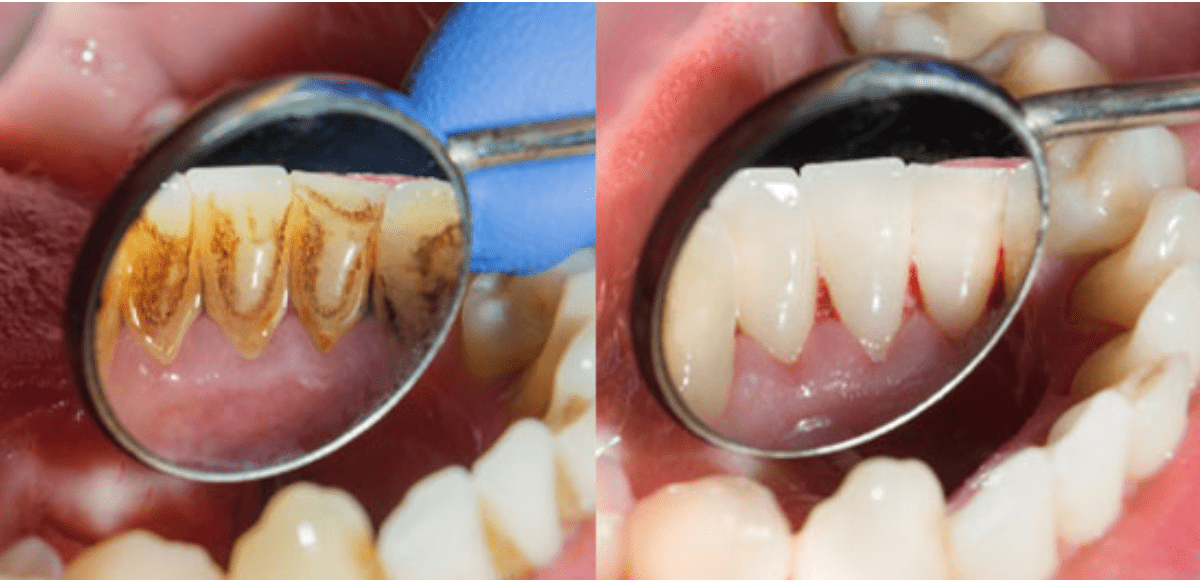

. Menggosok gigi secara teratur membantu membersihkan sisa makanan atau plak yang menempel pada gigi sehingga gigi menjadi bersih dan sehat. Setelah itu gigi tersebut akan ditambal dengan menggunakan bahan-bahan khusus seperti komposit resin porselen emas atau perak. Filling dilakukan dengan terlebih dahulu membuang bagian gigi yang rusak.

Administrator April 5 2022 TRADISIONAL Leave a comment 61 Views. Filling atau tambal gigi merupakan tindakan yang paling umum dilakukan untuk mengatasi gigi berlubang. Kedua teh ini memiliki kandungan fluoride alami yang bertugas menjaga enamel gigi juga kandungan polifenol yang bisa membantu melindungi gigi dengan mencegah terjadinya plak pada gigi sehingga gigi berlubang pun bisa dihindari.